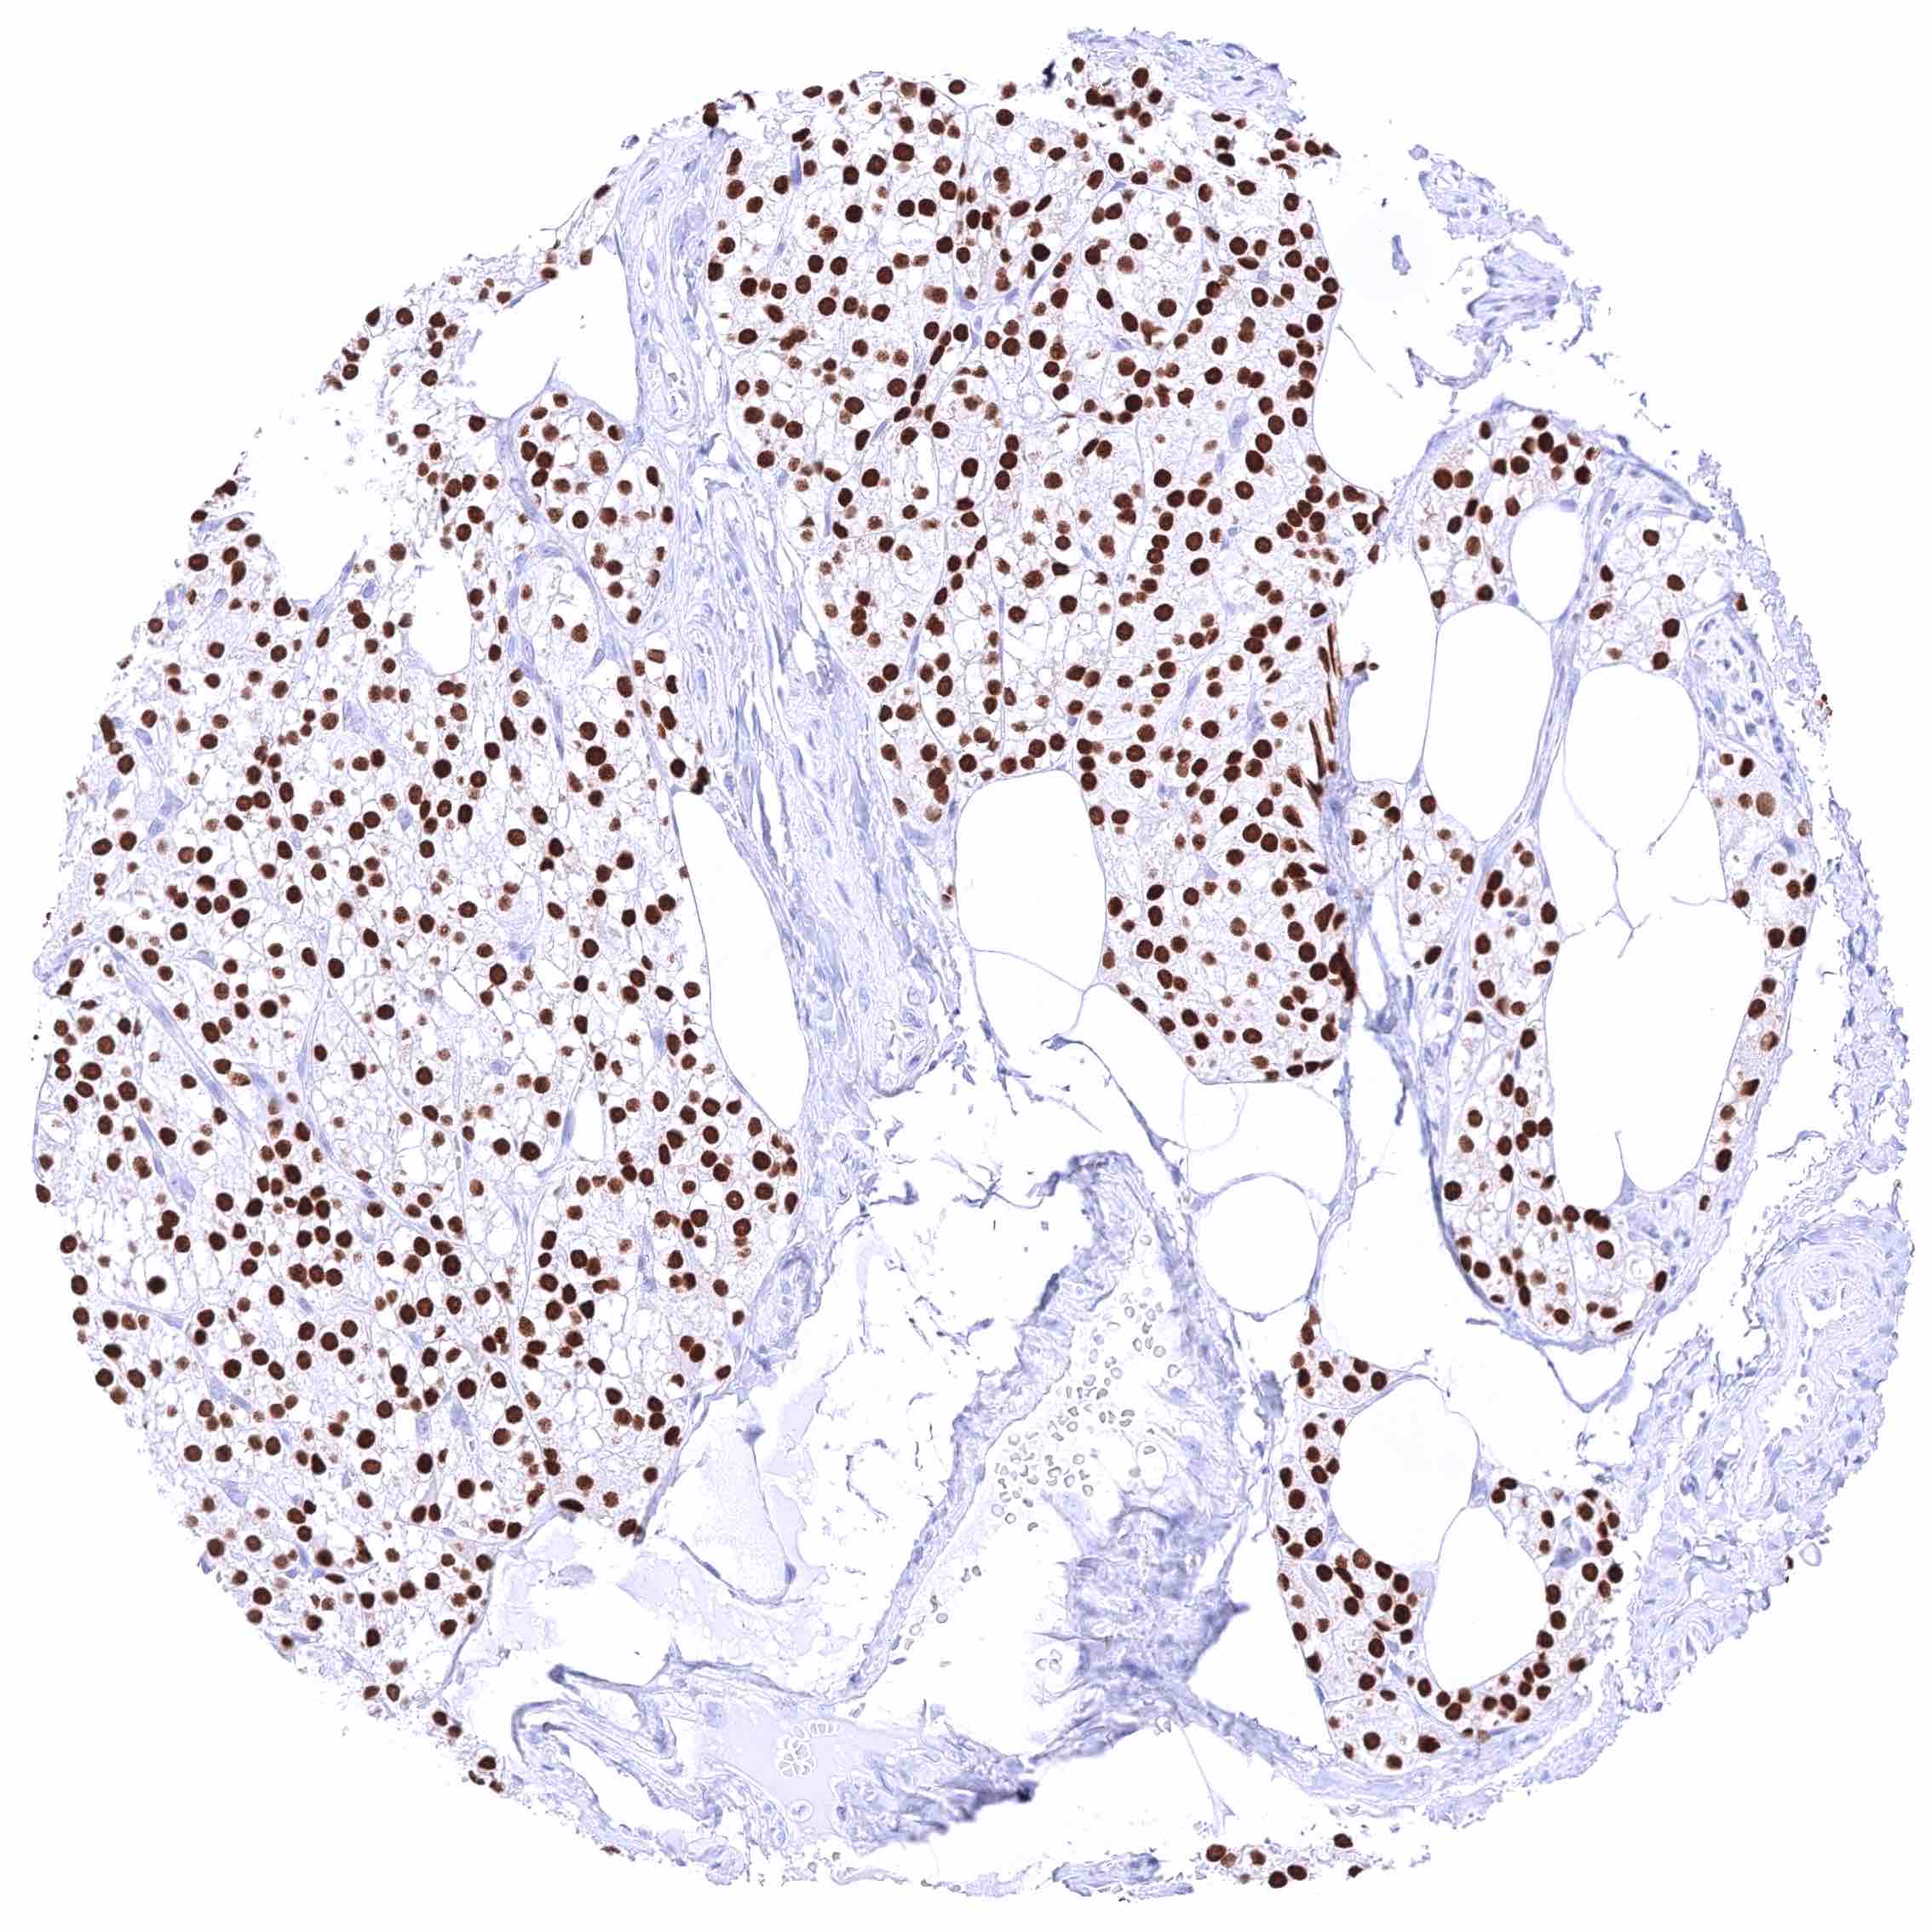

Parathyroid gland – Strong nuclear GATA3 positivity of all epithelial cells. .jpeg

Placenta, early – Strong nuclear GATA3 positivity of trophoblastic cells.

Placenta, mature – Strong nuclear GATA3 positivity of trophoblastic cells.